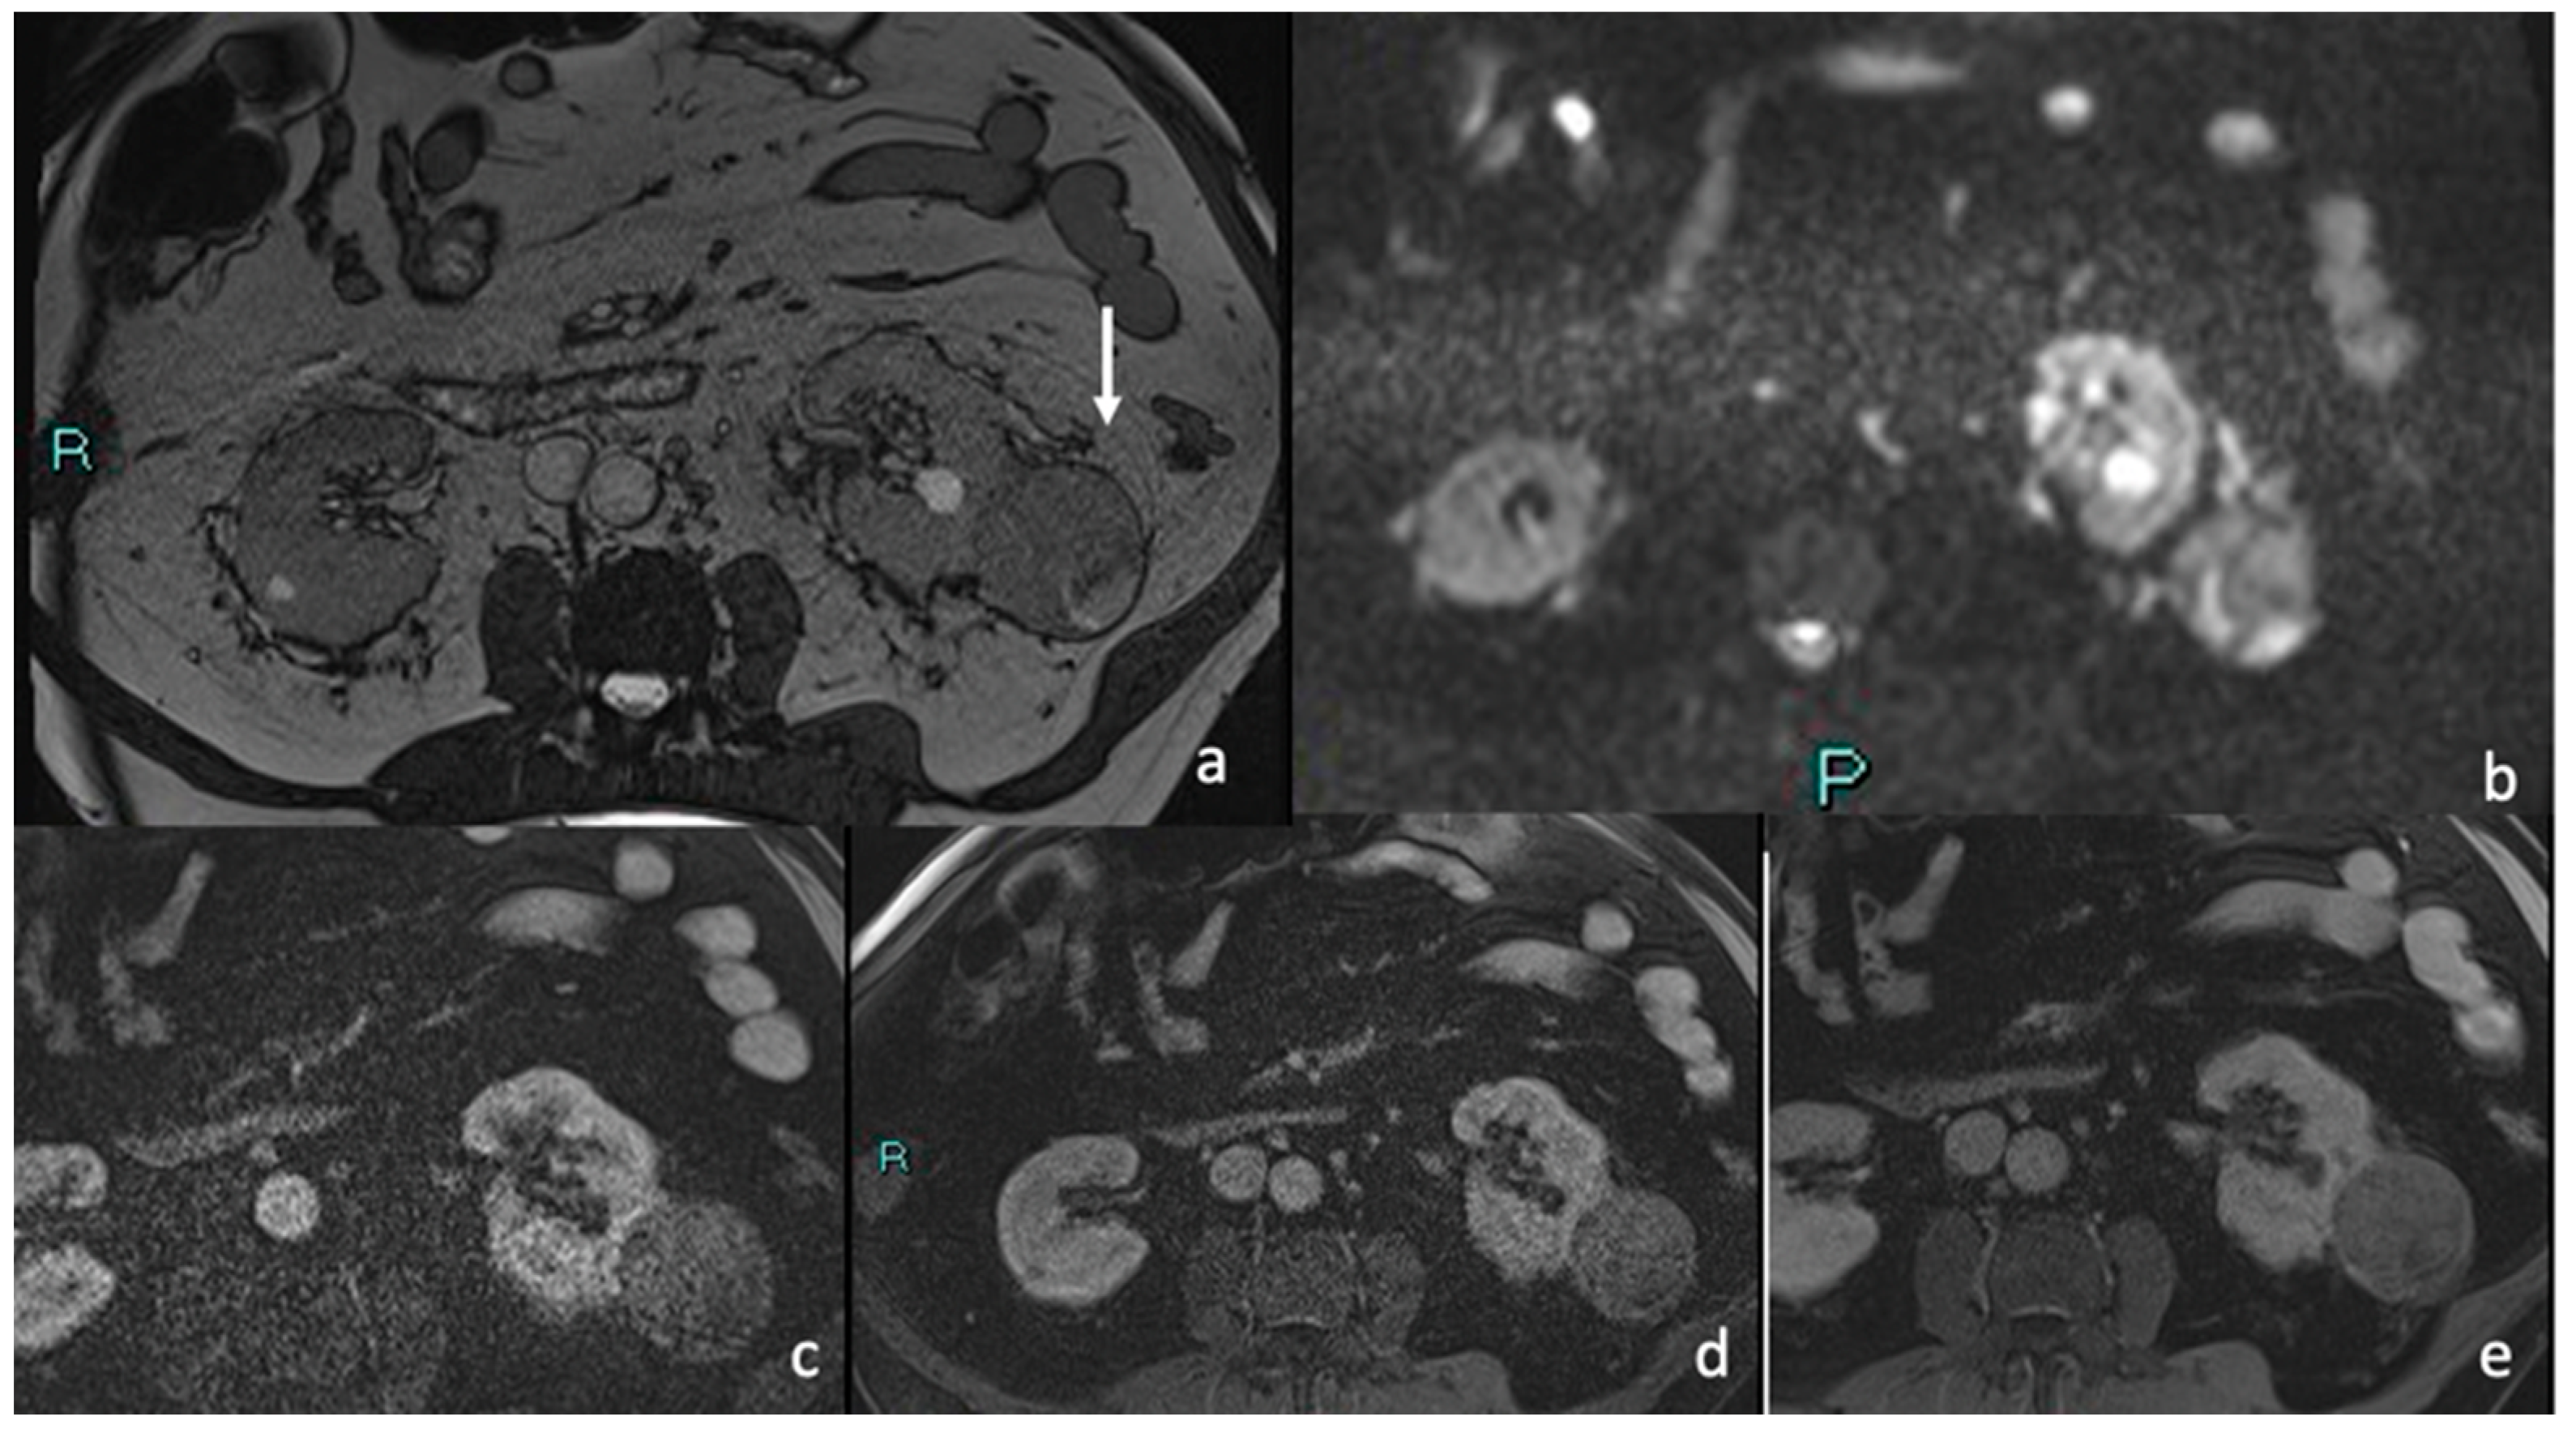

3.4. MRI

Signal Intensity, Homogeneity, and Contrast Enhancement

| Signal Intensity and Homogeneity | Assessed on T1 and T2 sequences (hypotense, hyperintense or isointense compared to renal parenchyma). Homogeneity assessed paying attention to regions of necrosis, cystic degeneration, or hemorrhage (low signal on T2). Hyperintense on DWI sequences and hypointense on ADC maps, indicating marked restriction. |

| Contrast Enhancement | Enhancement measured across dynamic phases. Pre-contrast and peak post-contrast signal intensity. |

| MRI FEATURES | % | n. | p Value |

| 88.9% 7.4% 3.7% | 24 2 1 | p < 0.05 p > 0.05 p > 0.05 |

| 29.6% 11.1% 59.5% | 8 3 16 | p > 0.05 p > 0.05 p < 0.05 |

| 100% | 27 | p < 0.05 |